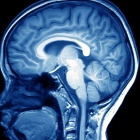

Sin duda alguna es un excelente estudio de la función neurologica 2000 a 3500 dependiendo de la duración mucho importa quién lo ve. Saludos y que se mejore !!